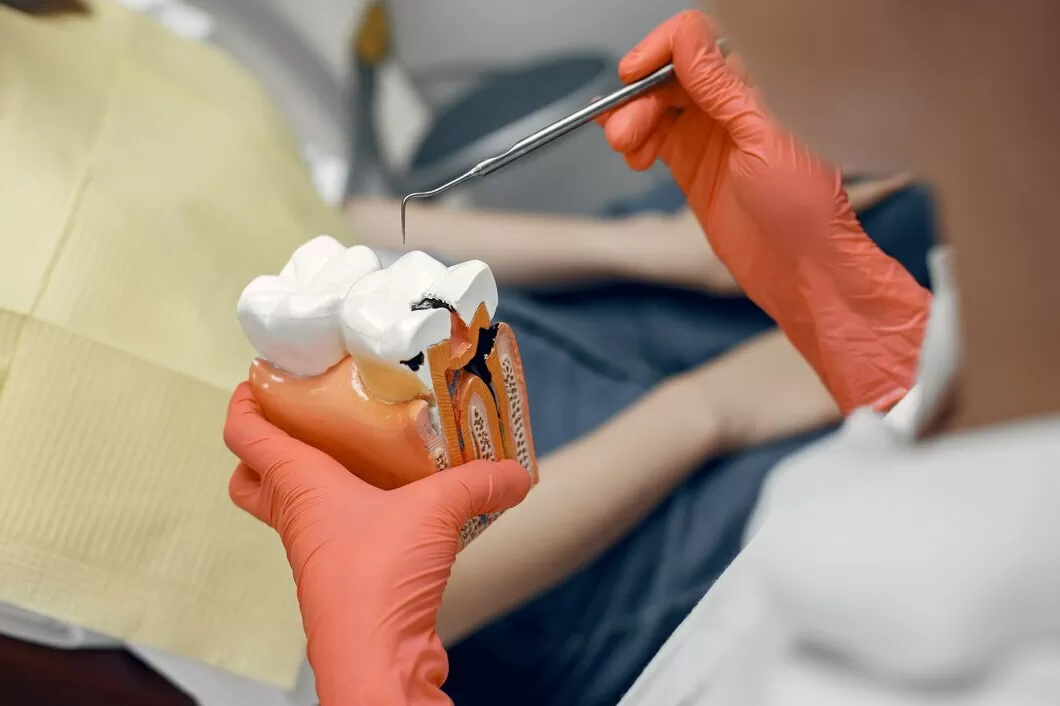

Болезни зубов

В разделе описаны все известные поражения зубов в коронковой части (эмаль, дентин, шейка и пульпа), заболевания пульпы, корня, периодонта и альвеолы. В статьях собрана информация о симптомах, причинах, лечении (профессиональном и народном в домашних условиях) и профилактике любой зубной беды. Рекомендуем не заниматься самодиагностикой и тем более самолечением! Помните, что запущенные проблемы с зубами всегда поражают десны, об этом читайте в соседнем разделе Заболевания десен.